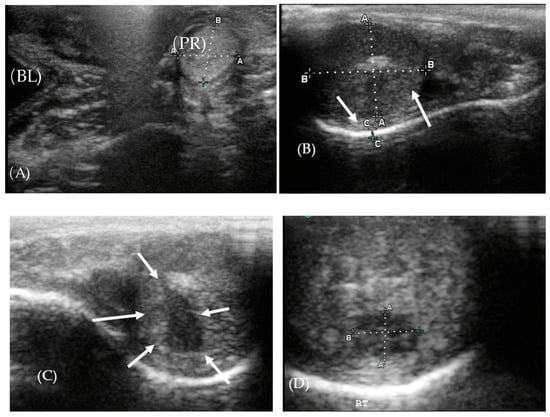

3.2. Ultrasonography of the Reproductive Tract